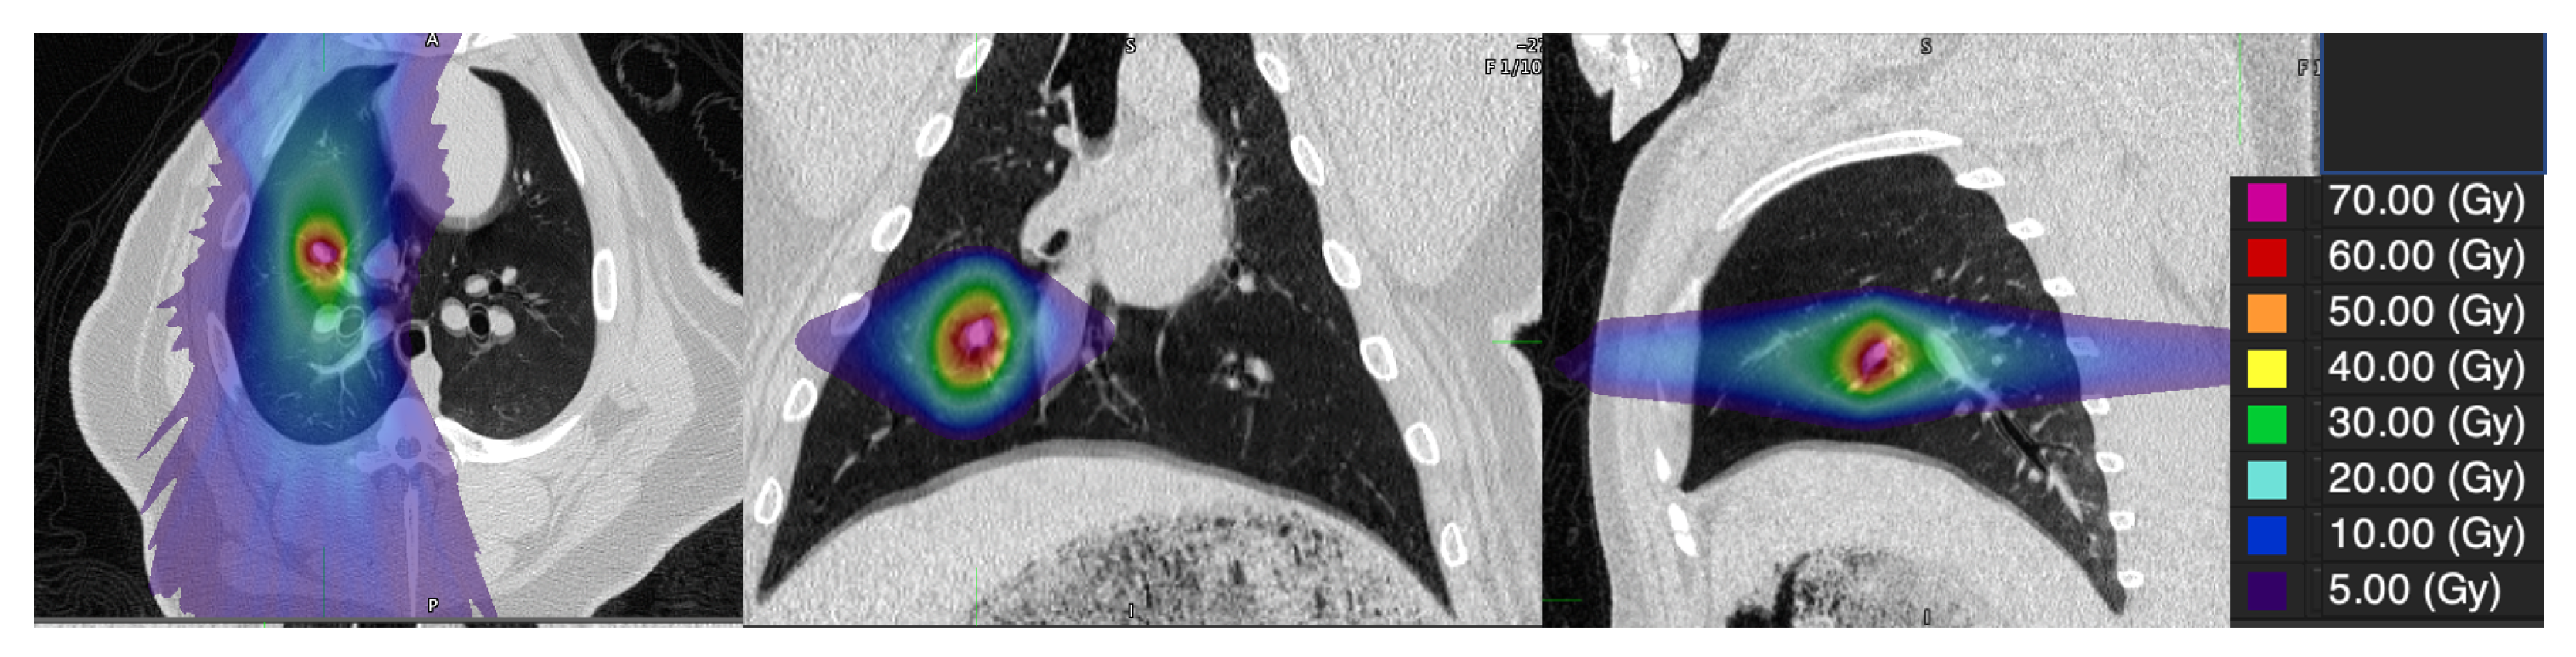

2.3. Swine Treatment